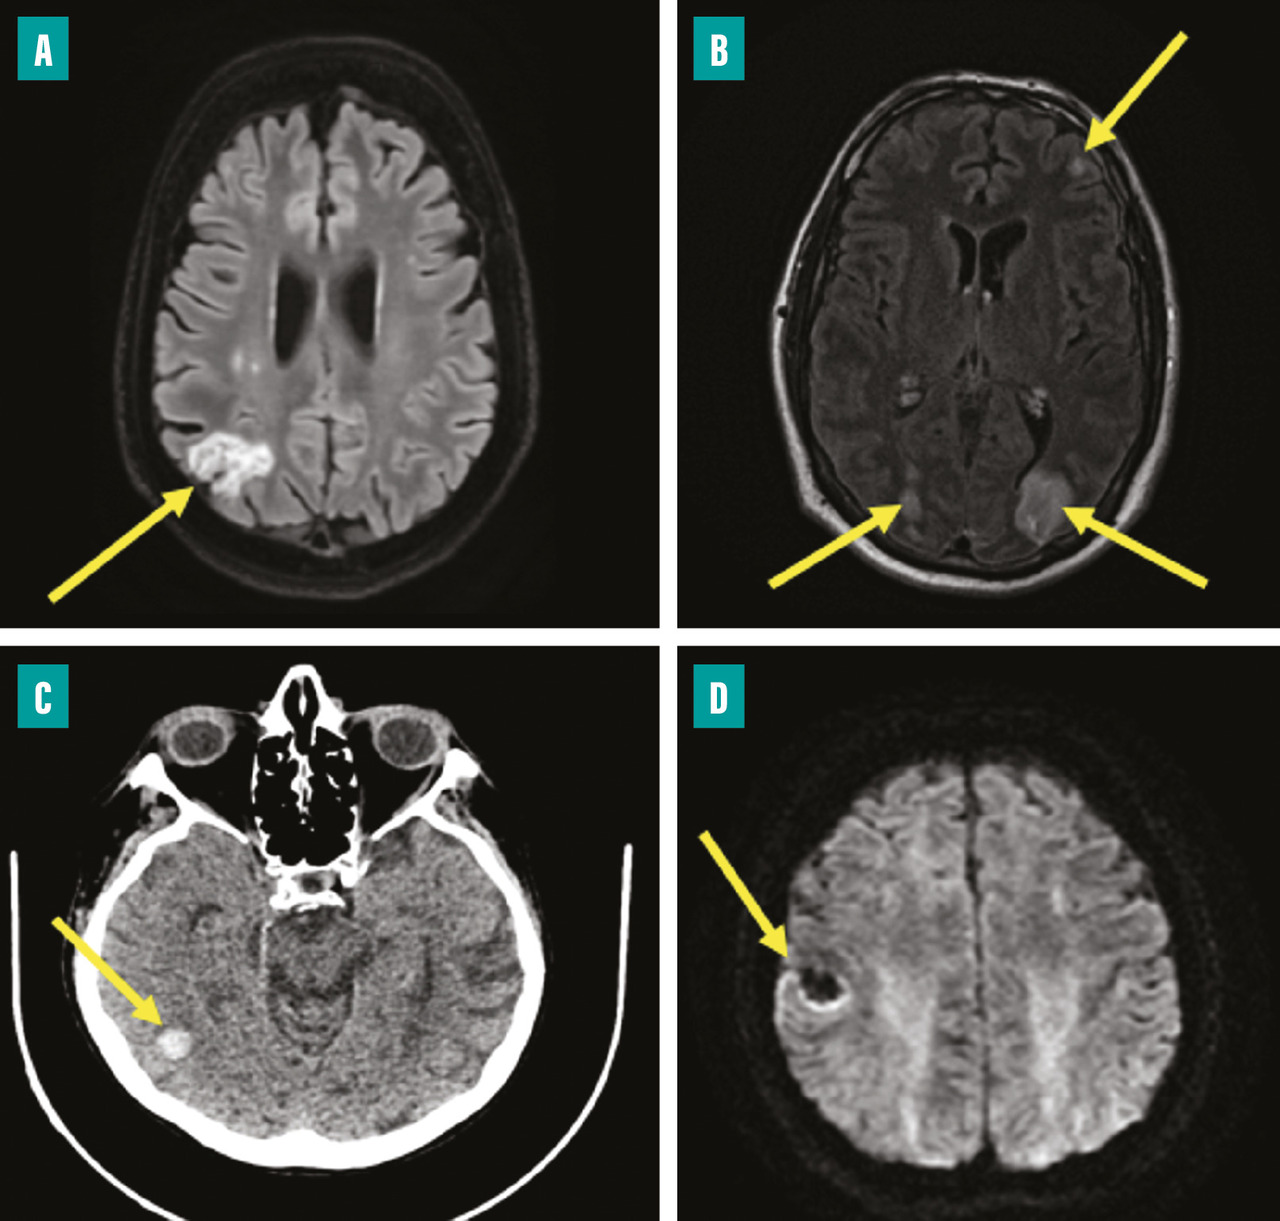

L’atteinte neurologique peut être de plusieurs formes (fig. 5 ) :6,7

– accident vasculaire cérébral (AVC) ischémique (25 à 50 %) ;

– AVC hémorragique (12 à 30 %) ;

– méningite (4 à 8 %) ;

– abcès cérébral (3 à 5 %) ;

– anévrysme mycotique (3 à 10 %).

Les signes révélant les accidents neurologiques sont multiples : déficit focal isolé, AVC fébrile, convulsions ou encore état comateux. L’AVC peut être cliniquement silencieux dans 20 à 30 % des cas, d’où l’importance d’une imagerie cérébrale systématique dans l’EI.7,10

Un scanner cérébral avec injection doit être réalisé devant tout trouble neurologique. Le bilan est complété par une angio-IRM (imagerie par résonance magnétique) cérébrale qui permet de mieux préciser la nature des lésions (abcès, anévrysmes mycotiques…) et de mettre en évidence des lésions de petite taille, parfois non visibles au scanner. Ces examens permettent de rechercher une éventuelle rupture de la barrière hémato-encéphalique dont la présence est une contre-indication à la chirurgie valvulaire en urgence. L’artériographie cérébrale est réalisée, en complément de l’IRM s’il existe un anévrysme mycotique pour discuter son éventuelle exclusion par voie endovasculaire.